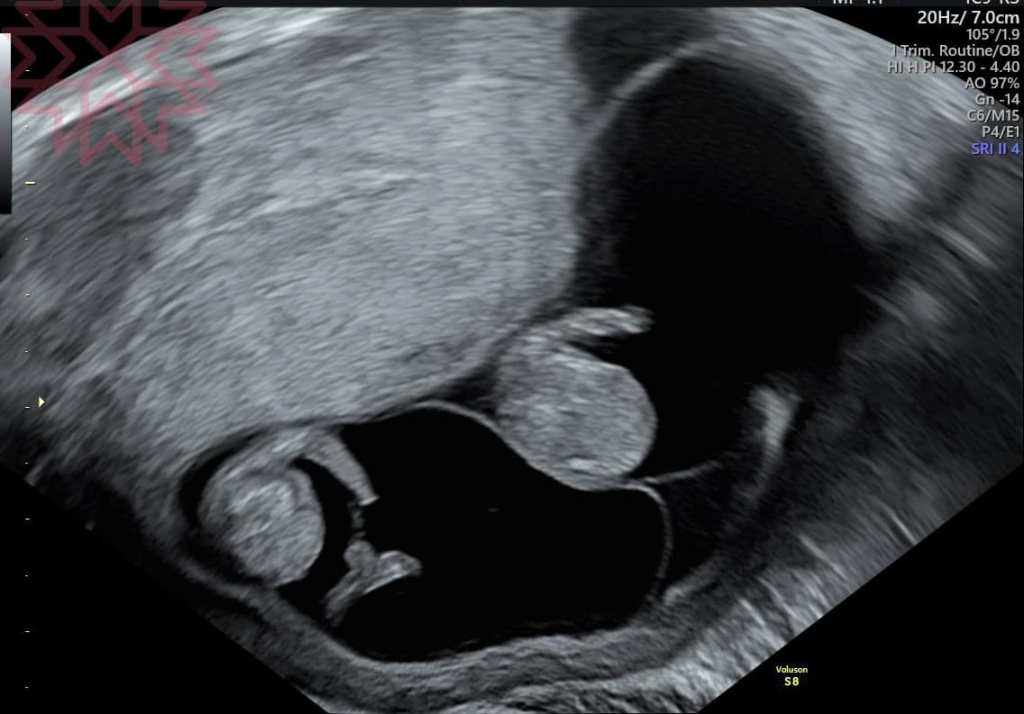

這到底是哪一種雙胞胎?

我無法用你傳上來的超音波照片做診斷

這牽扯到超音波的解析度

(看這個是用陰道超音波還是腹部超音波有時候也差很多

就是用超音波照片只能看到某一個角度跟切面

但真正的超音波診斷還是必須親自操作用不同的角度去做判斷才會準確

超音波解析度有差嗎?

當然有

如果你不信的話請看一下第二張我自己準備的超音波照片

應該不是專業的都可以看得出來有差別吧

(你應該可以清楚的看出羊膜

(而這個就是判斷的重點